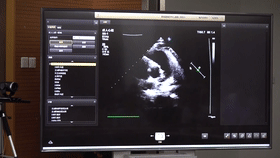

5G遠(yuǎn)程會診現(xiàn)場,西安國際醫(yī)學(xué)中心心內(nèi)科張衛(wèi)澤主任、超聲科陳姍姍主任打開4K高清顯示器,屏幕上立刻出現(xiàn)了商洛國際醫(yī)學(xué)中心的B超畫面,一位醫(yī)生正在為患者做心臟B超,隨著探頭的轉(zhuǎn)動,超聲機(jī)器上的畫面清晰可見,雖然兩家醫(yī)院相距一百多公里,但畫面流暢,沒一點拖沓。

“真的太棒了”張衛(wèi)澤表示,“沒有延時與卡頓,清晰的好像在一個房間內(nèi)進(jìn)行病歷討論”。陳姍姍非常興奮,直呼很震撼。她告訴筆者,“以前做遠(yuǎn)程會診,經(jīng)常遇到畫面和聲音不在一個頻道、畫面模糊等情況,遇到疑難病歷只能將影像拷下來回去研究,現(xiàn)在好了這些問題都將一次性解決。”